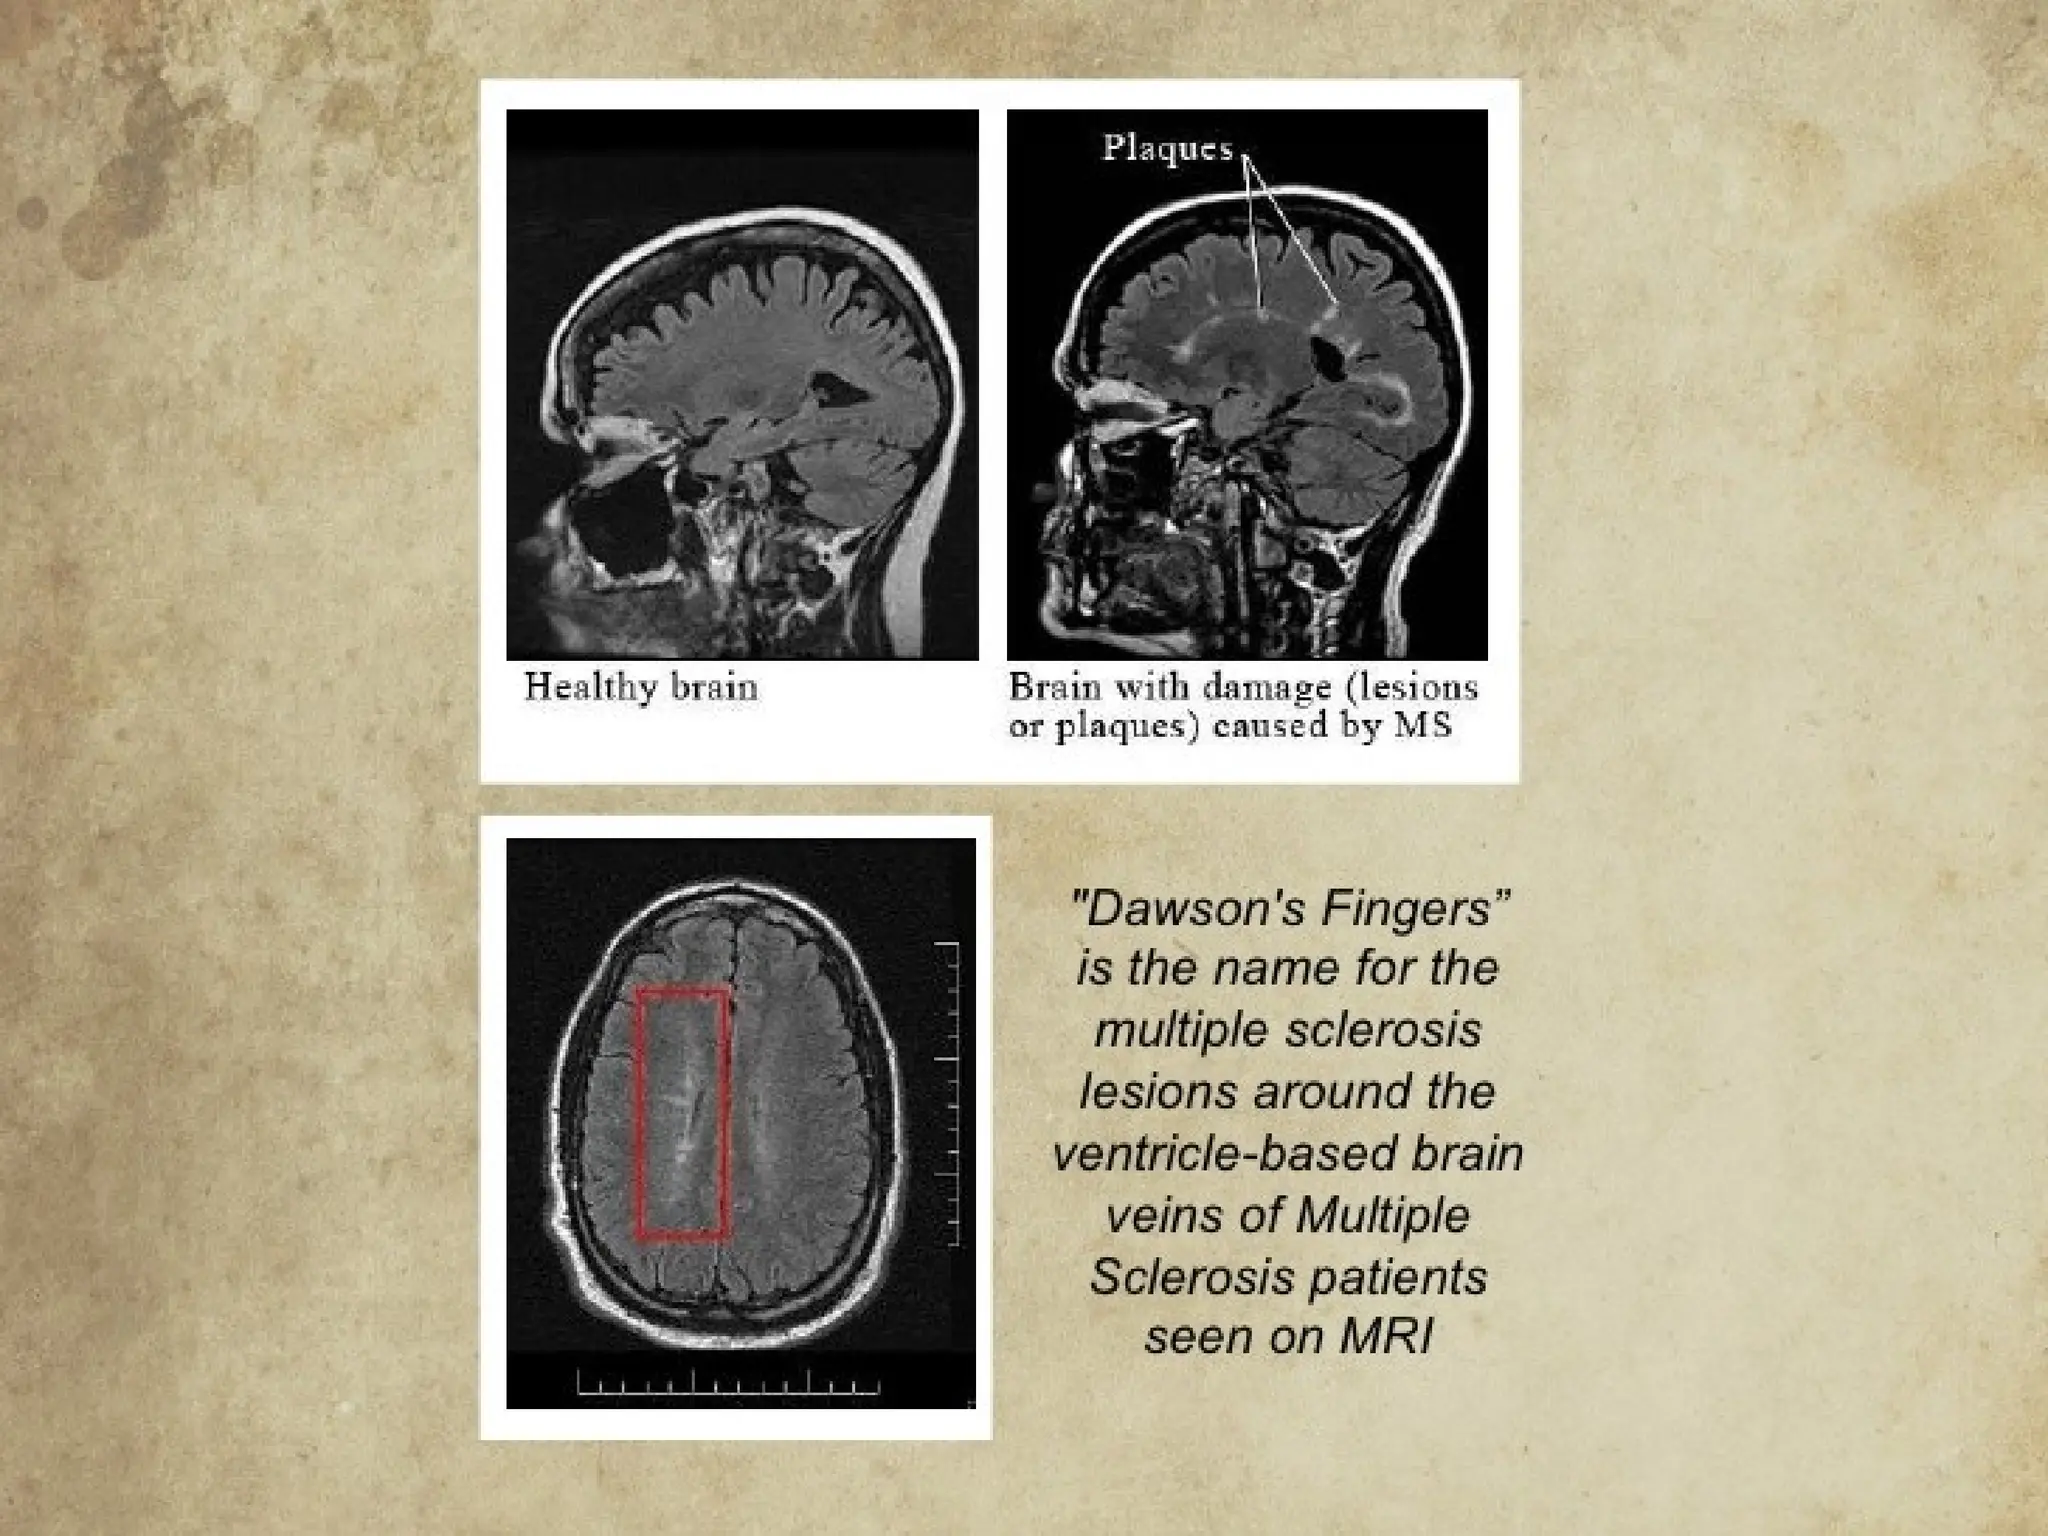

Results: Repeated attacks on the axon, the

surrounding myelin sheath eventually causes

scarring or plaques that interrupt or even

block nerve impulses, causing progressive

cognitive/physical disability

• #9 Although scientists are still working out the details of the immune attack in MS, the basic steps involved appear to be as follows: Misguided immune cells—called T cells—cross the blood-brain barrier (BBB) into the CNS. The BBB, which is thought to consist of walls of capillaries in the CNS, usually prevents or slows the passage of undesirable substances (e.g., disease-causing organisms) from the blood into the CNS. These T cells release chemicals that rally other immune system forces that attack the myelin coating around the nerve cells, as well as the cells that manufacture myelin. This attack causes inflammation and then destruction. The nerve fibers themselves also come under attack. Once the myelin and nerve fibers have been damaged, nerve signals are slowed or stopped. MS lesions (damaged areas as seen on MRI) form, with hardened scars or plaques that may impair normal myelin repair processes.